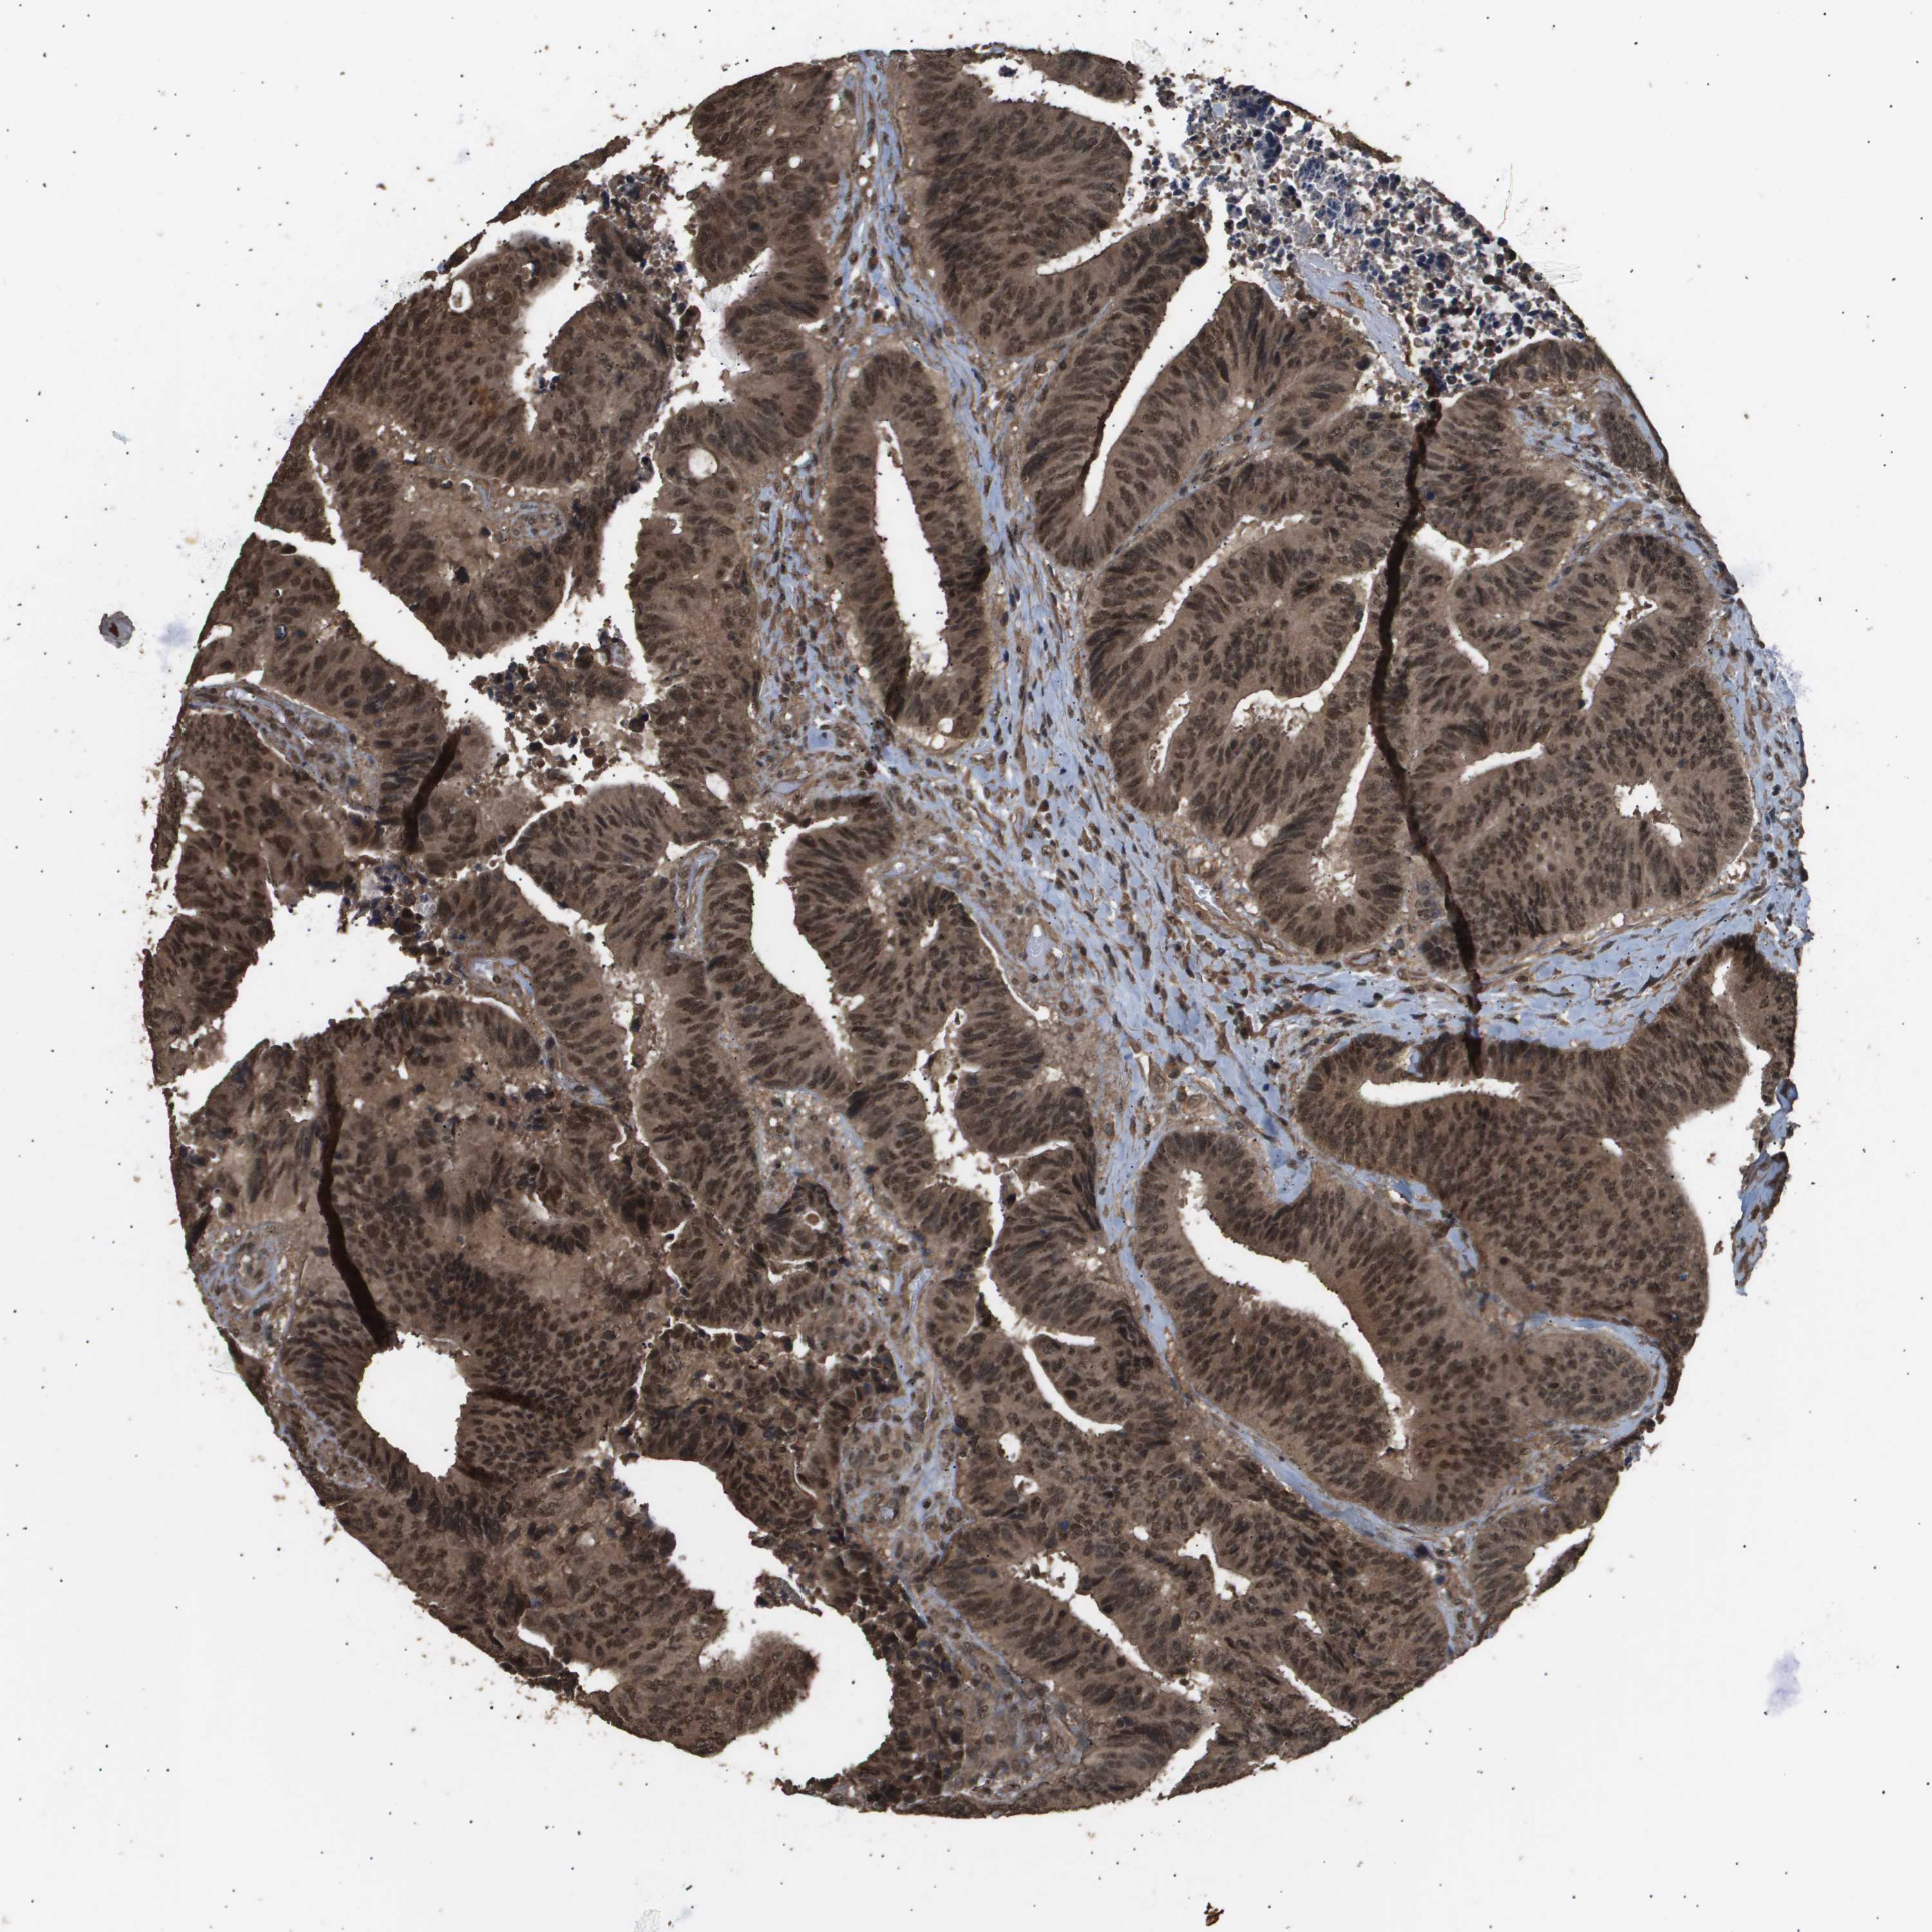

CANCER COLORECTAL CANCER Show tissue menu

Colorectal cancer

Human cancer